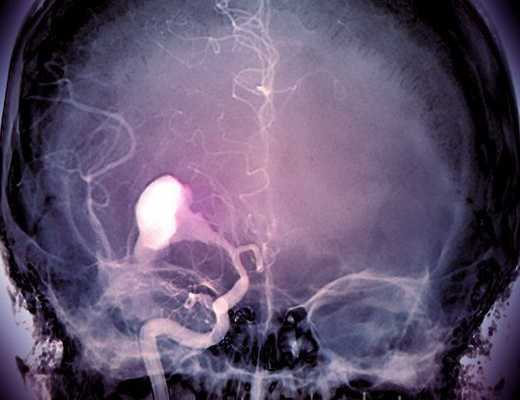

Аневризматические расширения сосудов имеют особую морфологию - шейка, тело, купол. Причиной заболевания являются отложения жировых комплексов внутри сосудистой стенки. Болезнь называется атеросклерозом, обуславливает много осложнений со стороны мозга, сердца. Повреждение стенки приводит к нарушению проницаемости. Попадание внутрь интерстиция крови обуславливает расслоение. Между отдельными слоями скапливаются сгустки, форменные элементы. Движение крови создает давление на тонкую стенку. В определенный момент сосуд может не выдержать. Появление небольшого разрыва сопровождается кровоизлиянием. Массивное кровотечение приводит к гибели.

Контрастное МРТ для аневризмы мозга - оптимальный вариант диагностики патологии. Томограммы отражают полную морфологию - мешотчатое, веретеновидное расширение артериальной стенки. Даже нативное МР-сканирование позволяет достоверно верифицировать аневризму. Контрастирование улучшает визуализацию.

Томограммы показывают размеры аневризмы. Образование свыше 10 мм опасно разрывом.

- Пространственную структуру, взаимосвязи отдельных деталей выявляет МР-ангиография. Болюсная инъекция контрастного препарата создает четкое изображение артерий и вен;

- Тромбированное и нетромбированное аневризматическое расширение выявляют путем изготовления множества срезов. Режим трехмерного моделирования позволяет построить пространственную проекцию объекта. Процедура помогает определить форму, размеры аневризмы;

- Комбинированное исследование (КТ и МРТ) после травм головы позволяет диагностировать тромбированные области артерии, измерить длину шейки, верифицировать размеры.

После тяжелой травмы ангиография проводится с целью изучения пространственных связей между разными физиологическими и патологическими образованиями. Магнитно-резонансная нейровизуализация проводится для верификации разрыва, тромбоза, аневризматического расширения артерии. Исследование дополнительно обнаруживает целый список патологии.